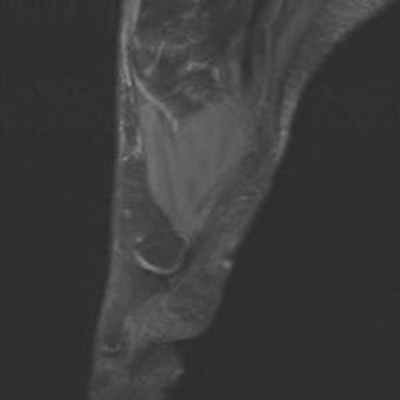

Боль в переднем отделе стопы правой ноги у пациентки 19 лет, в области головки 2-ой плюсневой кости.

Головка 2-ой плюсневой кости выглядит сплюснутой и расширенной с правой стороны в связи с болезнью Фрейберга.

Отсутствие внутрикостной отёчной инфильтрации по краям суставной щели плюснефалангового сустава. Напротив, следует отметить наличие внутрисуставного выпота.

Отсутствие бурсита между головками плюсневых костей или под ними.

Не обнаружено невромы Мортона или тендовагинита.